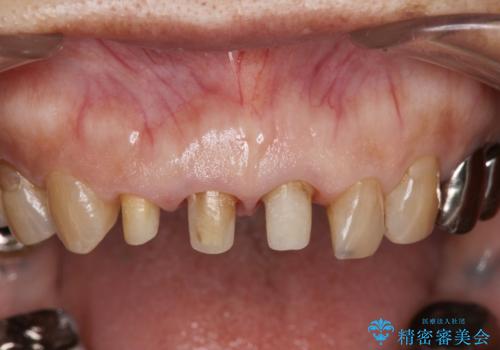

前歯の審美改善

- 孫娘の結婚式に合わせて前歯を綺麗にして写真映りをよくしたいと来院されました。

結婚式に合わせて根管治療からのやりかえを短期集中治療で計4回で終える計画を立てます。

- 40万円(仮歯・ファイバーコア・ジルコニアクラウン×3)費用は治療当時の料金となります